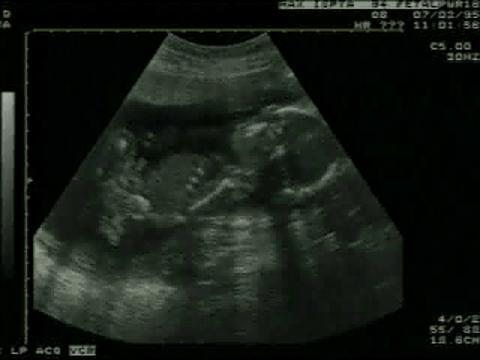

Fetal Ultrasound Scanning

Ultrasound scanning in pregnancy is used to evaluate the fetus. The fetal heart can be seen vibrating rapidly in the middle of the scan. The head can be seen on the right. Other body parts, such as the extremities and the rib cage, can be seen as the fetus moves within the womb.

Video from Cascom International, Inc.